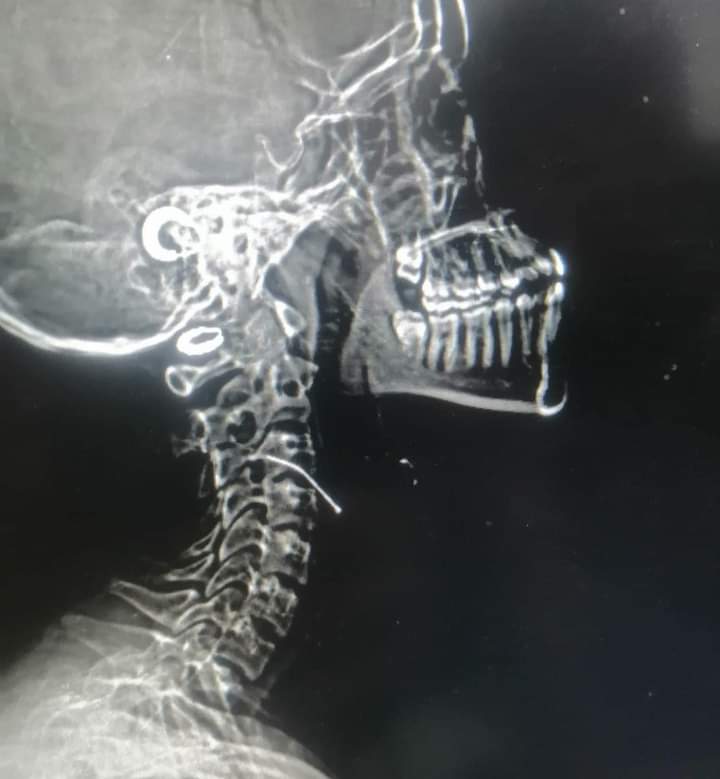

إنقاذ حياة طفلة ابتلعت "دبوس" بمستشفى الخارجة في الوادي الجديد

تمكن قسم جراحة الأنف والأذن والحنجرة بكلية الطب جامعة الوادي الجديد، من إنقاذ حياة طفلة تبلغ من العمر خمسة عشرة عامًا قامت بابتلاع دبوس حيث حضرت إلى طوارئ مستشفى الخارجة وتمكن الفريق باستخدام المنظار من استخراج الدبوس.

تكون الفريق من الدكتور حازم جمال نورالدين بقسم الأنف والأذن والحنجره والدكتور أشرف أخصائي التخدير بالمستشفى والدكتور محمود محمد علي مدرس مساعد بقسم الأشعه التشخيصية.